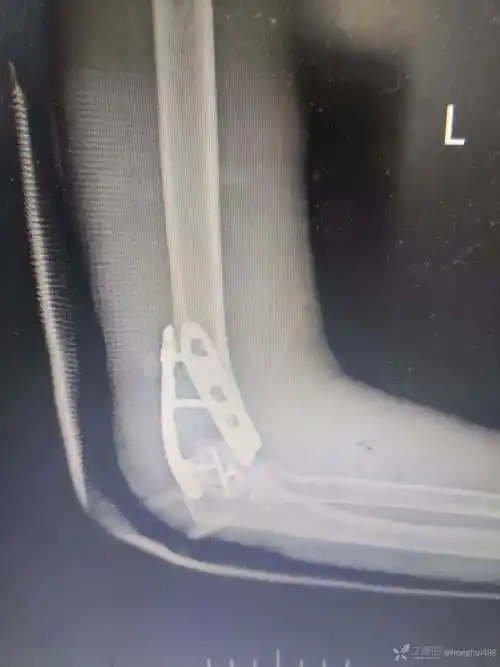

左三踝骨折手术治疗

三踝关节骨折脱位钢板固定